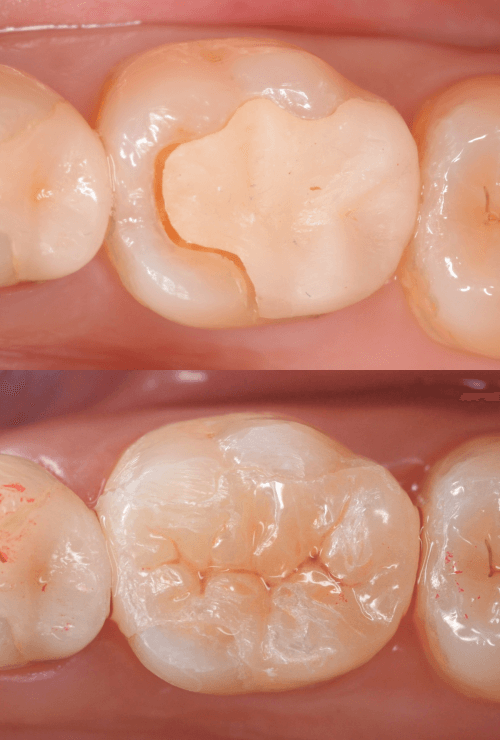

Case.29

舌のそばの虫歯とセラミック治療

下の奥歯が虫歯になった患者さんのケースです。

〇部が虫歯の部分です。

写真で見てわかるように、常に舌が歯に触っているような状況です。

このような場合、虫歯を見つけづらいですし、治療の難易度もあがります。

虫歯の治療を開始します。

隣の歯とのすき間を中心に広い虫歯になっていました。

虫歯治療後、特に症状もなく経過観察できましたので、つめものを作る治療に入ります。

セラミック治療をご希望されましたので、

小臼歯をE-MAX・インレー、

大臼歯をジルコニア・インレーで処置することになりました。

治療後の状態です。

自然な仕上がりで、患者さんにもご満足いただけました。